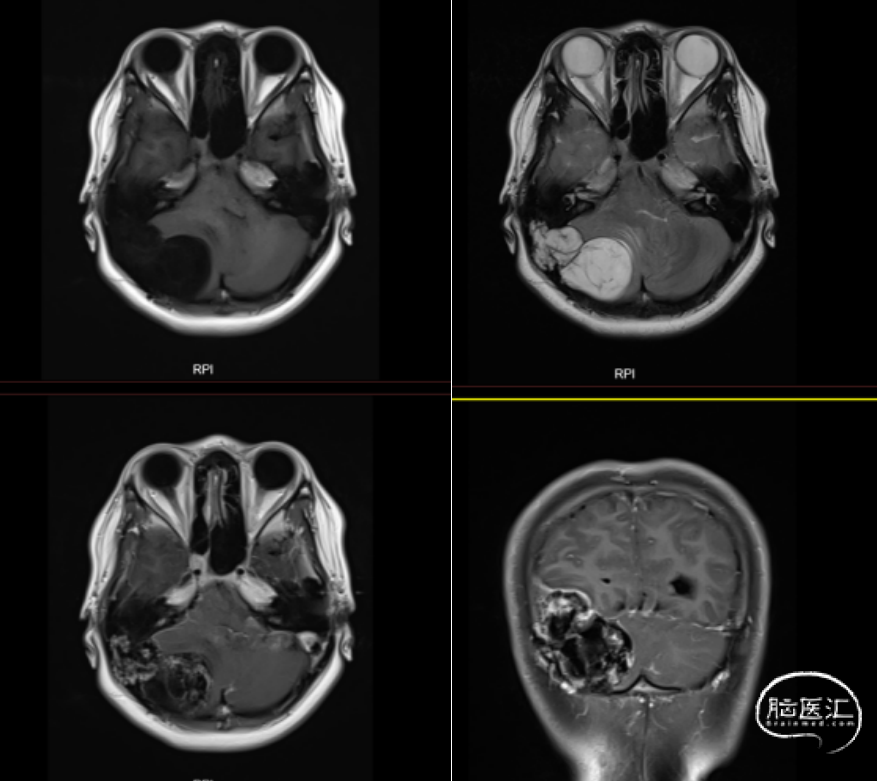

患者入院完善术前检查,头颅CT提示:右侧小脑半球-枕叶混杂密度肿块,大小约71*37mm,内见钙化,邻近颅骨骨质破坏、变薄,第四脑室受压(图1、图2)。进一步完善头颅增强MRI提示右侧颞枕部占位,脑外起源考虑,软骨肉瘤可能,血管瘤型脑膜瘤或血管瘤待排(图3)。

图3. 头颅增强MRI图像,见右侧颞枕部混杂长T1长T2信号肿块,大小约60*37mm,T1WI为低信号影,T2WI为高信号影,内见线样低信号影,增强后病变不均匀渐进性强化,临近脑实质及脑室系统受压,侧脑室和三脑室扩张积水。

本例颅内软骨黏液样纤维瘤的影像学表现典型,CT与MRI可辅助术前评估肿瘤边界及与周围结构的毗邻关系。CT可清晰显示边界清晰的溶骨性病变,伴边缘硬化及周围骨结构改变,但钙化检出率较低(约13%),多见于颅面部CMF或年轻患者[1]。组织学中钙化检出率更高(约35%),颅底CMF的细胞内钙化比例可达75%[2],本例患者CT与组织学均证实钙化存在(图1)。 MRI在确定病变范围方面比CT更有效。肿瘤在T1加权像上呈低信号,T2加权像上呈高信号,增强后显著强化,周围可能有软组织肿胀。通常由于纤维、软骨样和粘液样成分的组成不同,T2-STIR或T2加权脂肪抑制图像显示中等到高信号[5]。此外,MRI能清晰显示病变周围正常血管结构,对制定手术方案至关重要[2]。